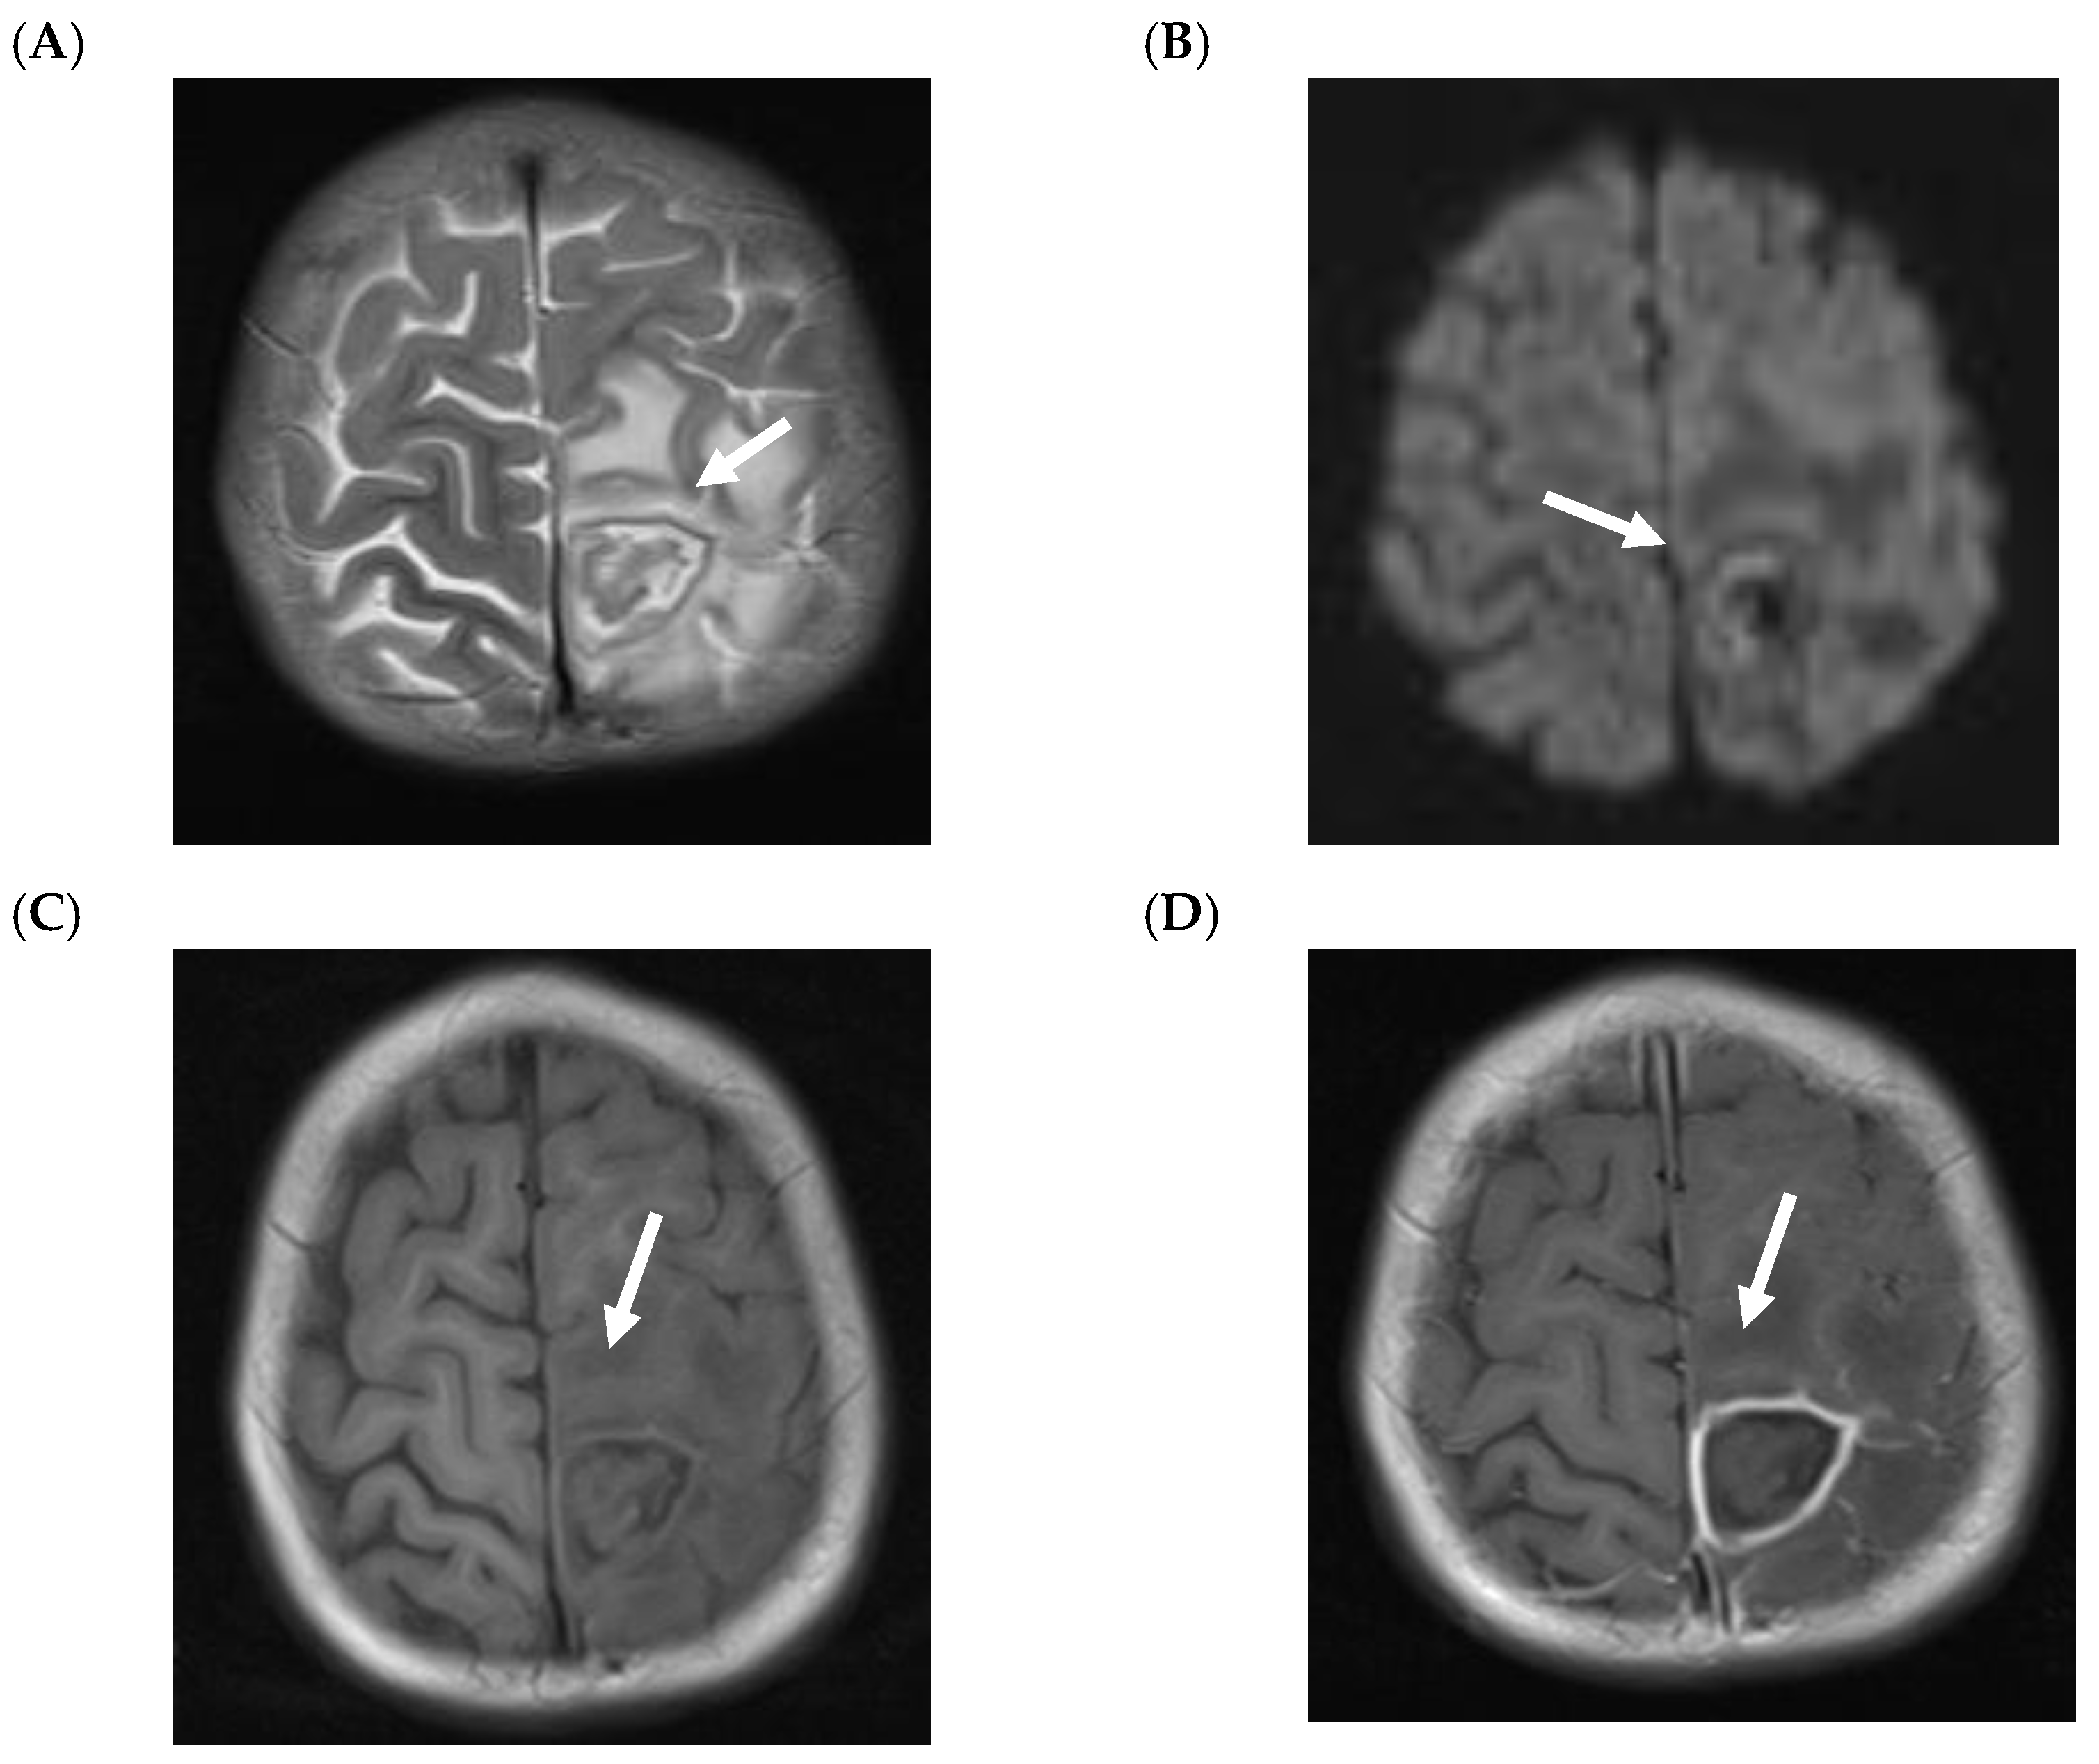

5.2. CNS Manifestations

- Antulov, R.; Dolic, K.; Fruehwald-Pallamar, J.; Miletic, D.; Thurnher, M.M. Differentiation of pyogenic and fungal brain abscesses with susceptibility-weighted MR sequences. Neuroradiology 2014, 56, 937–945. [Google Scholar] [CrossRef]

- Mathur, M.; Johnson, C.E.; Sze, G. Fungal infections of the central nervous system. Neuroimaging Clin. N. Am. 2012, 22, 609–632. [Google Scholar] [CrossRef]